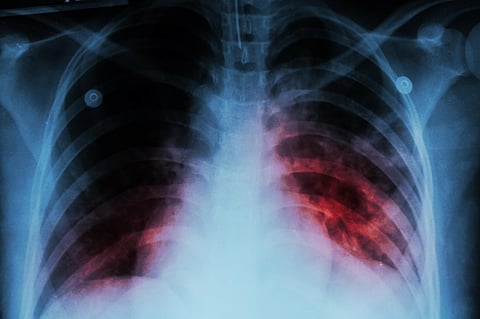

India’s efforts have resulted in reduction of TB incidence by 16% in 2022 (from 2015) almost double the pace at which global TB incidence is declining (which is 8.7%). The mortality of TB has also reduced by 18% during the same period in India and globally. The World Health Organization has made a downward revision of the TB mortality rates from 4.94 lakhs in 2021 to 3.31 lakhs in 2022, a reduction of over 34%.

The report notes that India’s intensified case detection strategies have resulted in the highest ever notification of cases – in 2022, during which, over 24.22 lakh TB cases were notified, surpassing the pre-COVID levels.